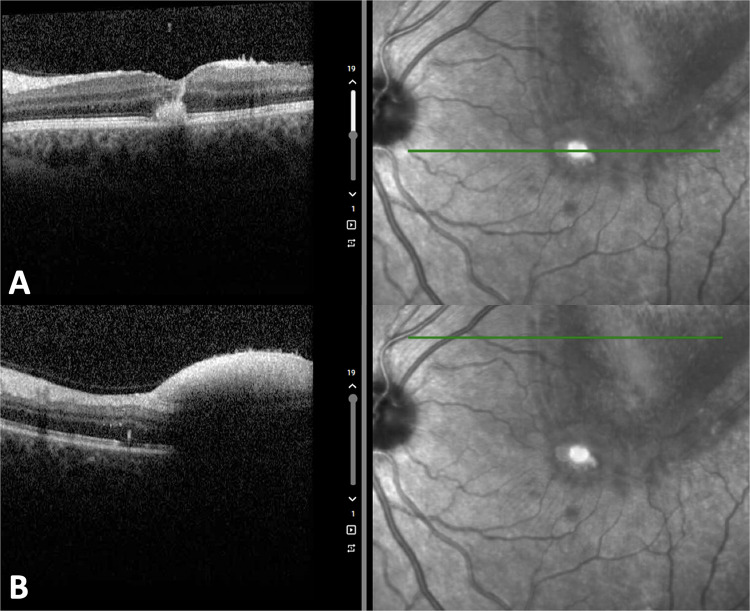

The current case report and literature review evaluate the management and optimal mode of delivery for Valsalva retinopathy in pregnancy. A 30-year-old primigravid female was discussed presenting with Valsalva retinopathy in the left eye at 35 weeks of gestation after dry heaving with a visual acuity of 20/200. Four weeks after cesarean-section, she had worse central vision and improving residual hemorrhage. A literature review of 25 Valsalva retinopathy cases showed all patients treated with laser posterior hyaloidotomy or pars plana vitrectomy achieved complete resolution (median of 1.5 weeks, p = 0.08), compared to 67% of untreated eyes (median of 5 months, p = 0.08). Average final visual acuity was 20/30 for the treated and untreated cohorts. Intervention may result in faster recovery time but with similar final visual acuity. Four (15%) cases of Valsalva retinopathy were incited by vaginal delivery. However, neither vaginal delivery nor cesarean section resulted in recurrence/worsening of premacular hemorrhage. These findings may help guide treatment of challenging Valsalva retinopathy cases in pregnancy.